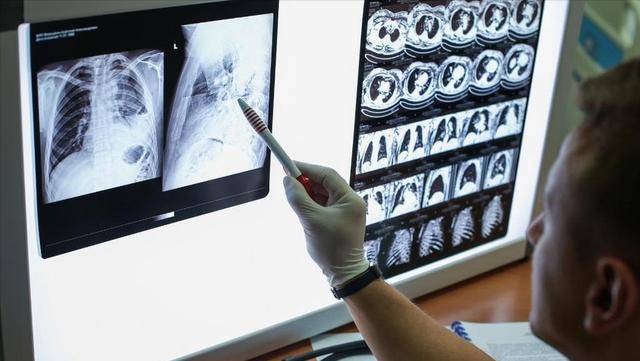

在体检报告上看到“肺结节”这三个字,不少人立马陷入了紧张,甚至脑子里直接联想到“癌”这个词。说实话,能不怕吗?毕竟肺是呼吸的要害部位,一点风吹草动都让人不安。

但其实,大多数肺结节并不代表恶性,有不少是良性结节或者炎症后留下的痕迹。问题是,它们可不全是无害的,如果对该做的检查掉以轻心,那就真可能错过了早期发现肺癌的机会。

说白了,发现了肺结节,并不等于“马上住院”或者“动手术”,反而最重要的是学会“盯着它看”——这也是医生最强调的一件事:随访复查。

肺结节的发展并不是一蹴而就的,它有一个缓慢的演变过程。而在这过程中,有三个关键时间点,医生们反复提醒不能错过。很多患者不太在意这些时间安排,觉得自己没不舒服就无所谓了,可一旦错过了其中某一个点,后悔都来不及。